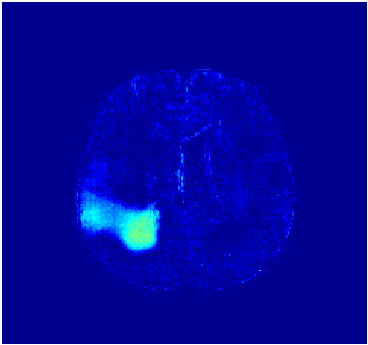

We observe that the generated normal-looking from ANT-GAN can also be used to directly segment the image, since the only difference between a synthesized normal-looking image and its real abnormal counterpart is region with the lesion. To illustrate this, we calculate the absolute difference between x𝑥x and 𝒢A2N(x)subscript𝒢A2N𝑥\mathcal{G}_{\rm{A2N}}(x) and show the segmentation after binary thresholding at 0.1 in Figure 9.

(a) Tumor x𝑥x

(b) 𝒢A2N(x)subscript𝒢A2N𝑥\mathcal{G}_{\rm{A2N}}(x)

(c) Prediction

(d) Label

Figure 9: Example segmentation obtained by taking the absolute difference between the real tumor MRI x𝑥x and the generated normal-looking MRI 𝒢A2N(x)subscript𝒢A2N𝑥\mathcal{G}_{\rm{A2N}}(x), after binarization at a preset threshold.